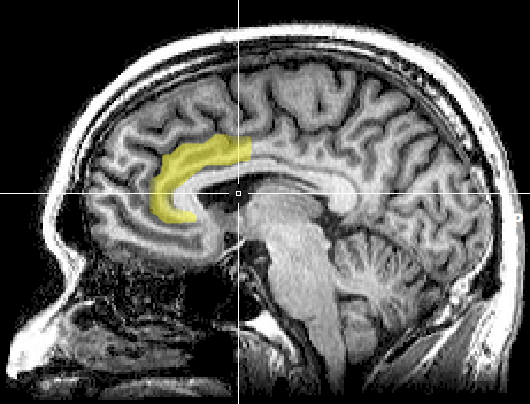

인지 부조화는 부정적 정동 상태를 유발하며, 이는 개인이 정신적 스트레스를 유발한 심리적 비일관성을 해결하기 위해 원인이 된 행동을 다시 생각하게 만든다.[3][114][110][111][112] 이러한 동기 부여 과정은 뇌의 왼쪽 전두엽에서 활성화된다.[113][114][115][116][111]

"인지 부조화 과정의 행동 기반 모델" 가설[127](Harmon-Jones, Levy, 2015)에 따르면, 심리적 부조화는 목표 지향적 행동을 방해하는 생각을 자극하는 결과로 발생한다. 연구자들은 모순된 행동을 할 때 심리적 스트레스를 유발하는 과제를 수행할 때 참가자의 신경 활동을 매핑했다. 참가자는 색상의 인쇄된 이름을 소리 내어 읽었는데, 인지 부조화 발생을 위해 색상의 이름은 참가자가 소리 내어 읽는 단어와 다른 색상으로 인쇄되었다. 그 결과, 실험이 심리적 부조화를 유발했을 때 참가자들은 전대상피질에서 증가된 신경 활동을 경험했다.[127]

기술 발전으로 심리학자들은 기능적 자기 공명 영상(fMRI) 등의 기술을 이용하여 인지 부조화의 생체역학을 연구할 수 있게 되었다. 연구에 따르면, 인지 부조화의 원래 이론을 뒷받침하며, 반대 태도 반응에서 전대상 피질이 등쪽 전대상 피질과 앞쪽 섬피질을 활성화하는 심리적 갈등 이론을 뒷받침한다. 뇌의 해당 영역의 활성화 정도는 개인의 심리적 태도 변화 정도에 의해 예측된다.[118]

인지 부조화의 발생은 전두엽의 신경 활동과 관련이 있으며, 분노라는 감정과도 관련이 있다. 기능적으로 분노는 좌전두엽의 신경 활동을 동기 부여한다.[114][31] 인지 부조화와 분노 사이의 관계는 인지 부조화를 일으키는 사회적 상황을 개인이 통제할 때 발생하는 좌전두엽의 신경 활동에 의해 뒷받침된다는 연구 결과도 있다.[114][123][122]

전대상피질 활동은 오류가 발생하고 모니터링될 때뿐만 아니라 고차원적 사고의 한 형태로 자아 개념과 행동적 갈등이 있을 때 증가한다.[124] 연구에 따르면 높은 선택권 조건의 참가자들은 낮은 선택권 참가자보다 좌전두엽의 더 높은 수준을 보였다. 인지 부조화의 초기 경험이 전대상피질에서 나타날 수 있으며, 이후 좌전두엽이 활성화되어 분노를 줄이기 위해 접근 동기 부여 시스템을 활성화한다는 것이다.[124][125]

하몬존스(Harmon-Jones, 2004)의 "분노와 인지 부조화에 대한 연구가 비대칭 전두엽 뇌 활동의 동기 부여 기능 이해에 기여하는 바" 연구에 따르면, 인지 부조화의 발생은 전두엽의 신경 활동과 관련이 있으며, 이 뇌 구조는 분노라는 감정과도 관련이 있다.[122] 기능적으로 분노는 좌전두엽의 신경 활동을 동기 부여한다.[114][31] 동기 부여의 방향성 모델을 적용한 "분노와 행동 접근 시스템"(2003) 연구는 인지 부조화와 분노 사이의 관계가 인지 부조화를 일으키는 사회적 상황을 개인이 통제할 때 발생하는 좌전두엽의 신경 활동에 의해 뒷받침된다는 것을 나타냈다. 반대로, 개인이 심리적으로 스트레스가 되는 자극을 통제하거나 바꿀 수 없다면, 상황을 바꿀 동기가 없어져 사회적으로 부적절한 행동과 같은 다른 부정적 정서가 인지 부조화를 관리하기 위해 발생한다.[114][123][122]전대상피질 활동은 오류가 발생하고 모니터링될 때뿐만 아니라 고차원적 사고의 한 형태로 자아 개념과 행동적 갈등이 있을 때 증가한다.[124] 좌전두엽의 활동이 증가할 것이라는 예측을 검증하기 위한 연구가 수행되었다. 대학생들은 높은 선택권 또는 낮은 선택권 조건에 따라 논문을 작성해야 했다. 낮은 선택권 조건에서는 학생들이 대학교 등록금 10% 인상에 찬성하는 글을 써야 했다. 높은 선택권 조건에서는 학생들이 등록금 인상에 완전히 자발적인 선택인 것처럼 찬성하는 글을 쓰도록 요청했다. 연구자들은 인지 부조화가 이 시기에 가장 높기 때문에 학생들이 에세이를 쓰기 전에 EEG를 사용하여 분석했다. 높은 선택권 조건의 참가자들은 낮은 선택권 참가자보다 좌전두엽의 더 높은 수준을 보였다. 결과는 인지 부조화의 초기 경험이 전대상피질에서 나타날 수 있으며, 이후 좌전두엽이 활성화되어 분노를 줄이기 위해 접근 동기 부여 시스템을 활성화한다는 것을 보여준다.[124][125]